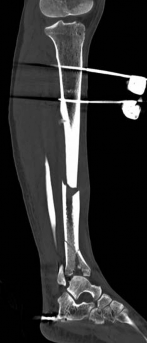

With the articular surface reconstituted, the surgeon's focus shifts to bridging the complex metaphyseal-diaphyseal dissociation. A pre-contoured anatomical locking plate is slid submuscularly or subcutaneously along the diaphysis using a MIPPO technique. The plate is positioned on the anterolateral or medial surface, depending on the preoperative plan and soft tissue constraints.

Image

The distal portion of the plate is secured to the reconstructed articular block. It is imperative that the distal locking screws are placed parallel to the joint space, forming a rigid subchondral raft that supports the articular cartilage. Fluoroscopy is utilized extensively to ensure no screws have penetrated the joint. Once the distal block is secured to the plate, the diaphyseal segment is aligned. Length, alignment, and rotation are restored using manual traction or the femoral distractor. The proximal portion of the plate is then secured to the diaphysis using a combination of non-locking screws (to pull the bone to the plate) and locking screws (to create a fixed-angle construct). The working length of the plate is maximized by leaving several screw holes empty over the zone of comminution, promoting secondary bone healing.